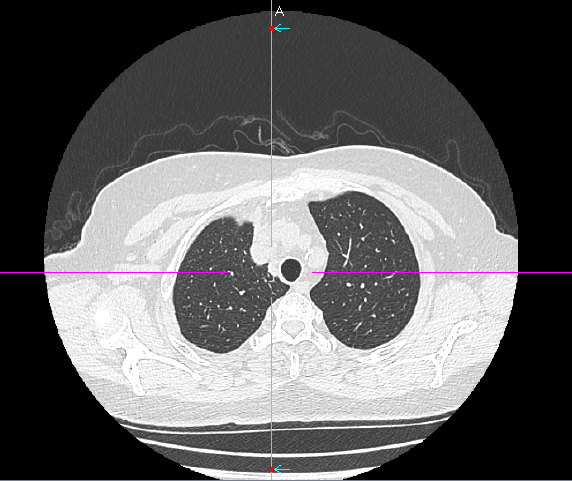

数月前,66岁的龚女士在肺癌术后随访复查中,胸部CT报告显示其右上肺新发实性结节一枚,并由刚开始发现时的5mm逐步增大至10mm。更棘手的是,这个结节位于右肺上叶尖段的纵隔胸膜下,位置极其“刁钻”。面对这份报告,患者龚女士陷入了深深的焦虑。因为其7年前因右中肺肿瘤行右中肺癌根治术,对于新发的实性结节为何种性质,是新发肺恶性肿瘤或是良性病变,亦或是原肺癌复发转移,目前均不能明确。辗转多家医院,得到的建议多为“定期观察,等待变化”或考虑创伤较大的传统穿刺活检,但结节位置非常深,单纯CT引导下定位穿刺很难精准到达,且需穿行的肺组织较多,创伤较大。

胸外科马海涛主任团队对龚女士的病情进行了深入细致的评估:结节虽小,但形态学特征具有风险,且结节逐步增大,结合既往肺癌病史,考虑肿瘤复发可能,“定期观察”方案会让患者持续承受心理煎熬。然而,传统的CT引导下经皮肺穿刺定位,对于如此深部、微小的结节,极易导致气胸、出血等并发症,风险极高。

马主任解释系统原理:“这套系统就像为我们医生的操作装上了‘肺部GPS’。它通过术前将患者的CT影像数据导入系统,构建出独一无二的肺部三维‘地图’。术中,在磁场的引导下,我们操控一根细如发丝的导航探头,经由患者的口腔、气管这一自然通道,毫无创伤地直达常规支气管镜无法到达的肺外周深处,精准地停靠在目标结节旁边。磁导航支气管镜的优势是决定性的。它实现了‘经自然腔道、无创抵达’,彻底避免了经皮穿刺可能引起的高达20%-30%的气胸风险,为定位深部结节提供了安全、精准的解决方案。”